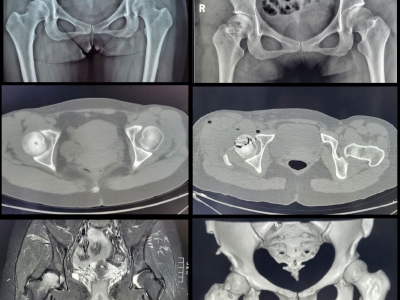

保髋手术治疗,股骨头坏死患者的福音来啦!